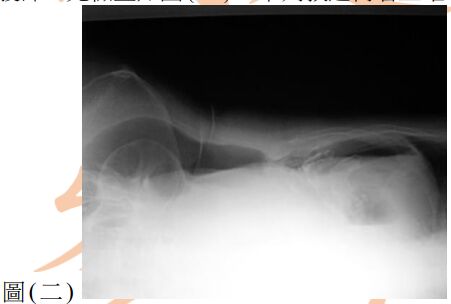

13. 80歲女性為長期糖尿病、高血壓及中風不良於行之病人,因急性腹痛來急診就醫,其平躺之腹部X光如圖(一),另一張左側躺之腹部X光檢查如圖(二),下列敘述何者正確? (A) 推測有腹腔積水,可能為腹腔腫瘤導致 (B) 推測有腹部脹氣,可能為腸阻塞導致 (C) 推測有腹腔積氣,可能為腹腔內中空臟器破裂導致 (D) 為正常腹部影像,只須持續追蹤